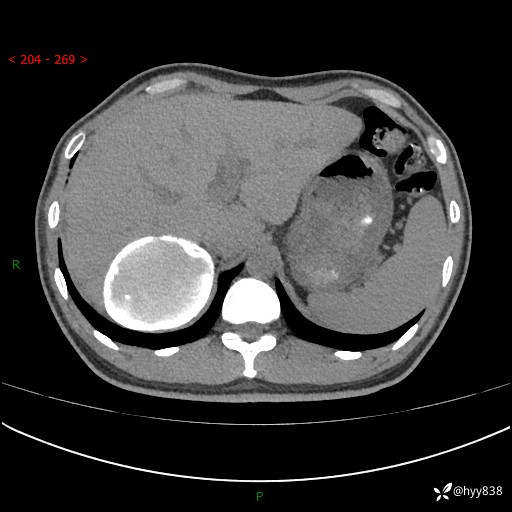

性别:男

年龄:50岁

简要病史:夜尿增多半月,发现肾功能异常1天,超声发现腹膜后占位

腹部CT平扫+增强